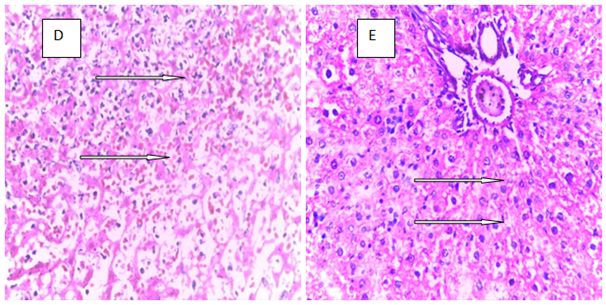

Histopathology is a critical part of the toxicologic and risk assessment of foods, drugs, chemicals, biologics, and medical devices. Histopathology is the study of the structural manifestations of disease at the light–microscopic level. Therefore, histopathology is necessarily a largely confirmative, descriptive and interpretive science. In addition to other applications, it can establish correlations between perturbations in serum biomarkers with morphologic alterations that may occur at tissue or organ levels due to a test substance.26 In the current study, histological assessment of the liver of control rats showed normal histology (Figure 1A). Also, the liver of rats treated with MT and ALA showed normal histology (Figure 1B, D). On the other hand, extensive hepatocyte necrosis was observed in the liver of LPV/r–treated rat (Figure1E), which is consistent with previous report.27 However, the liver of rats pretreated with MT and ALA showed absence of hepatocyte necroses (Figure 1G, H). This observation connotes that MT and ALA abrogate LPV/r–induced hepatic structural changes in pretreated rats. The protective effect of ALA observed in this study can be correlated with the study by Abdel Zaher et al.28 which reported that ALA restored liver structure in acetaminophen–intoxicated rats.28 Also, findings in the present study can be correlated with the reported protective effect of MT against cadmium–induced hepatic morphological alteration in rats.29 The mechanism by which LPV/r causes hepatic morphological alteration is not clear; however, it may involve OS, LPO and the stimulation of inflammatory cascade. Previous studies have reported hepatic OS leading to LPO in LPV/r–treated rats.30 OS is associated with oxidative radical production, which can result in histopathological lesions with a broad spectrum, ranging from hepatotoxity to hepatocellular carcinoma in an orchestrated manner. Evidence have shown that increased free radical concentration and activity are commonly observed during hepatic cell damage characterised by OS and LPO.31 LPO is a complex process that involves the formation and propagation of lipid radicals, the uptake of oxygen, rearrangement of double bonds in unsaturated lipids and the eventual destruction of membrane lipids.32 Exposure of hepatic proteins to reactive oxygen species can produce denaturation, loss of function, cross–linking, aggregation and fragmentation of connective tissues.33 In the current study, the protective effects of MT and ALA may be due to their free radical scavenging activities, inhibition of OS, LPO, and inflammation. Also, MT and ALA might have increased endogenous antioxidants activities and stabilized hepatic plasma membrane. ALA is a powerful antioxidant due to its ability to scavenge free radicals in both lipophilic and hydrophilic environments and to regenerate endogenous antioxidants. Also, it can inhibit LPO, OS, and prevent protein glycation and repair biomolecules damaged by oxidation.34,35 MT is an amphiphilic molecule that can freely cross cell membranes and enter cells where it has been reported to alter redox balance by increasing antioxidant synthesis, activity and scavenges free radicals. It can inhibit LPO thereby preventing DNA, lipid, and protein damage.36 Furthermore, experimental evidence showed that MT and ALA can inhibit inflammation–induced hepatotoxicity by up regulating anti–inflammatory mediators and inhibiting pro–inflammatory mediators.37,38

Figure 1 The above figures (A–G) are micrographs of the Hand E stained sections of the liver of control rat, and the liver of rats in the experimental groups. Normal hepatocytes were observed in the liver of control rat Figure 1A. Also, normal hepatocytes were observed in the liver of rats treated with melatonin, alphalipoic and a combination of melatonin, and alphalipoic (Figures 1E). On the other hand, extensive hepatocyte necrosis was observed in the liver of lopinavir/ritonavir-treated rat Figure 1E. However, normal hepatocytes were observed in rats pretreated with individual dose of melatonin and alpha lipoic acid respectively Figure 1F and G. Also, normal hepatocyte was observed in the liver of rats pretreated with a combination of melatonin and alpha lipoic (Figure 1H).